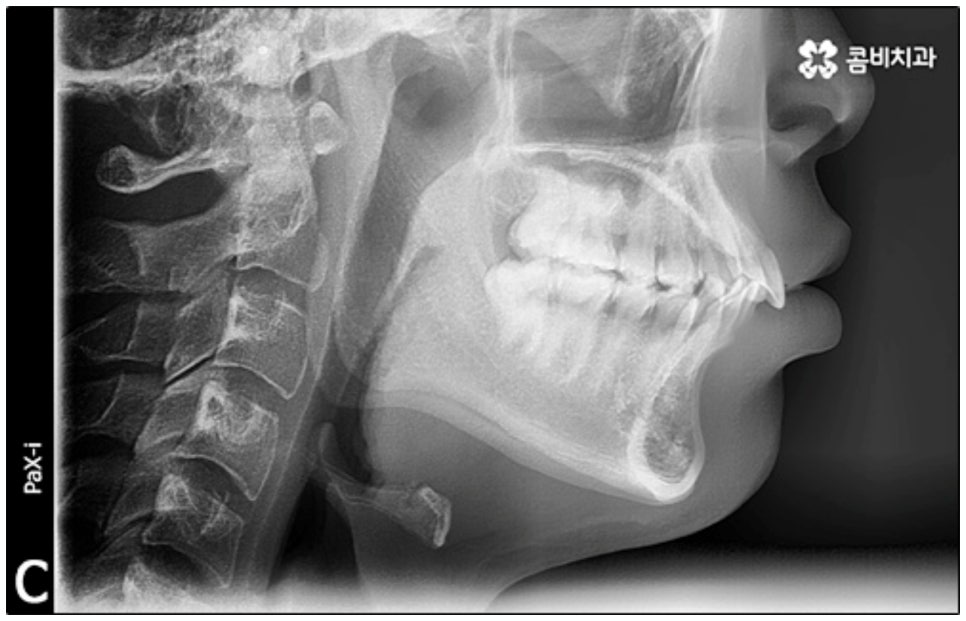

말씀드린 것과 같은 다양한 이점들이 있기 때문에 현재 본원의 교정 환자분들은 대부분 클리피씨교정 장치를 이용하여 치료를 진행하고 있습니다. 사진 역시 돌출입 교정을 위해 발치 후 클리피씨교정 장치를 이용하신 환자분의 케이스인데 시간이 지날수록 점차 앞니가 자연스럽게 들어가고 위아래 교합이 정확하게 맞아가는 것을 확인하실 수 있을 거예요.